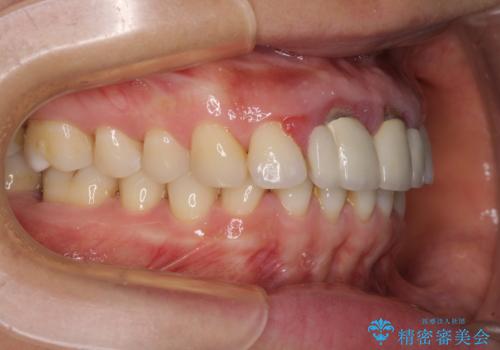

隙間をセラミックで閉じたら不格好で歯肉から出血 矯正治療と歯周外科で綺麗な前歯に

- 隙間の空いた前歯をセラミッククラウンで補隙したところ、歯肉から出血してしまい、何とかしたいとのことで来院された患者様です。

初めは前歯のみの処置で改善を希望されていたため、広範囲に処置範囲を広げることで歯の幅がバランスする治療を提案しましたが、削らなければならない歯が増えてしまうため、患者様と相談して全顎矯正により前歯のスペースを閉じていくこととしました。

不適合なクラウンが装着されていたため、歯周ポケットが深くなっていましたので、矯正治療前に歯周外科処置を行って歯周ポケットを除去し、矯正治療後にオールセラミッククラウンにて補綴治療を行うこととしました。

前歯の見た目はもちろん、出血や腫脹のない健全な前歯の状態を獲得することができました。